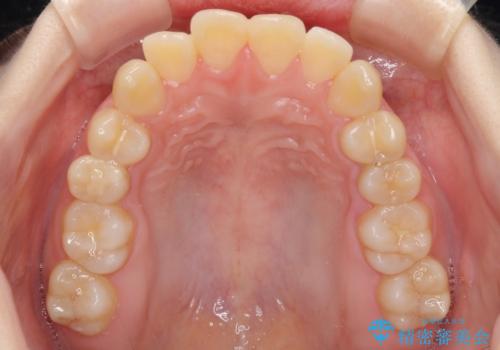

- 上下前歯が前方に飛び出しているとのことで来院された患者様です。

上下左右第一小臼歯4本を抜歯して、積極的に口元を引っ込めるよう、ワイヤー装置にて矯正治療を行うこととしました。

口元の突出感は著しく改善され、横顔の印象が大きく変化しました。